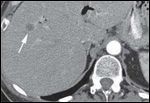

DR. PAUL RUSS: The initial CT scan of the abdomen with intravenous and oral contrast revealed a 2.7-cm, hypodense, hypovascular, solid mass in the head of the pancreas and also involving the uncinate process. In addition, there was dilatation of the pancreatic, intrahepatic and extrahepatic ducts without any evidence of distant metastatic or lymph node involvement. However, the second CT scan done, at the time of her clinic visit, showed post-surgical changes with an ill-defined soft tissue mass in the operative bed. There were also five new hypodense lesions in the liver, with the largest lesion in the anterior segment measuring 1.3 × 1.5 cm. There were two lesions in the dome, measuring 1.1 cm and 8 mm, along with two additional subcentimeter lesions in the right lobe (Figures 1A-1D, 2).

DR. PAUL RUSS: Because pancreatic adenocarcinoma is typically hypovascular compared to background pancreas and liver, the primary neoplasm is depicted as hypodense to the pancreas, and metastases as hypodense to the liver. However, some pancreatic adenocarcinomas remain occult, even with the use of advanced CT techniques, and in those cases the diagnosis can sometimes be surmised by using indirect, secondary signs like pancreatic and/or bile duct dilatation, and post-obstructive pancreatic atrophy. In this case, we see one of the typical hypodense lesions consistent with metastatic pancreatic cancer.